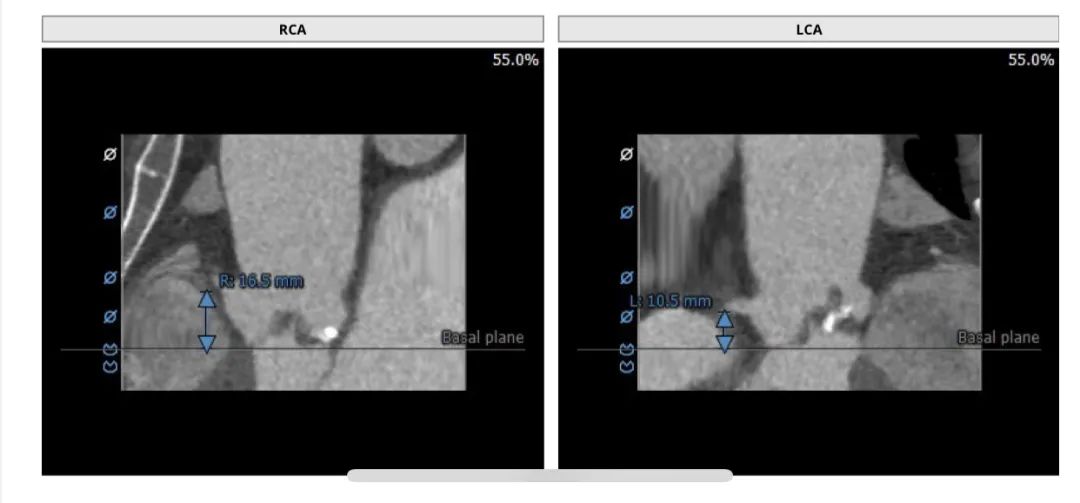

患者为功能型二叶瓣,中度钙化,瓣叶长且明显增厚,右冠高度16.5mm高度尚可,左冠高度10.5mm,左冠高度较低,且自体瓣叶冗长,评估冠脉风险较高。选择右股作为主入路。经过分析讨论,术者团队决定选择VenusA-Plus可回收输送系统,在瓣膜植入前,通过22mm球囊预扩张,确认瓣膜型号,同时评估瓣叶形态对冠脉开口的影响。

冠脉情况